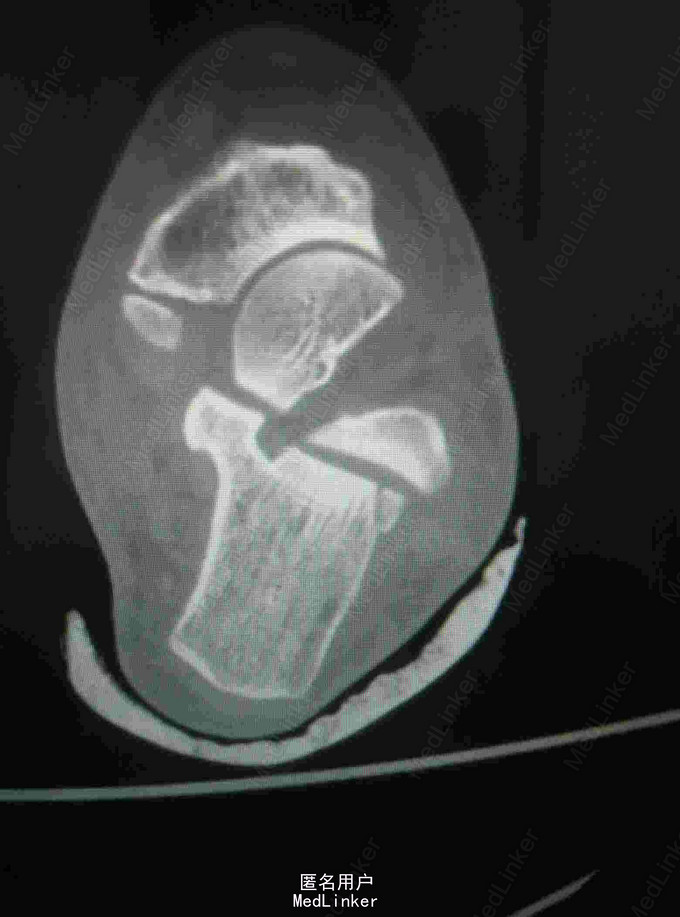

查体:左踝关节肿胀明显,局部皮肤压痛,无皮损及皮下淤斑,踝关节活动受限,各足趾感觉正常,足背动脉搏动存在。 辅查:我院CT提示距骨、足舟骨、跟骨骨折

诊断:左足距骨、足舟骨、跟骨骨折 治疗:距骨骨折切开复位内固定术

随访:石膏固定4-6周,3月内禁止负重,定期复查。 讨论:患者X线片对左足骨折显示不够清楚,基本常规行CT,可以看到明显的距骨骨折,累及关节面,需手术复位关节面。足舟骨以及跟骨骨折未明显移位保守处理。